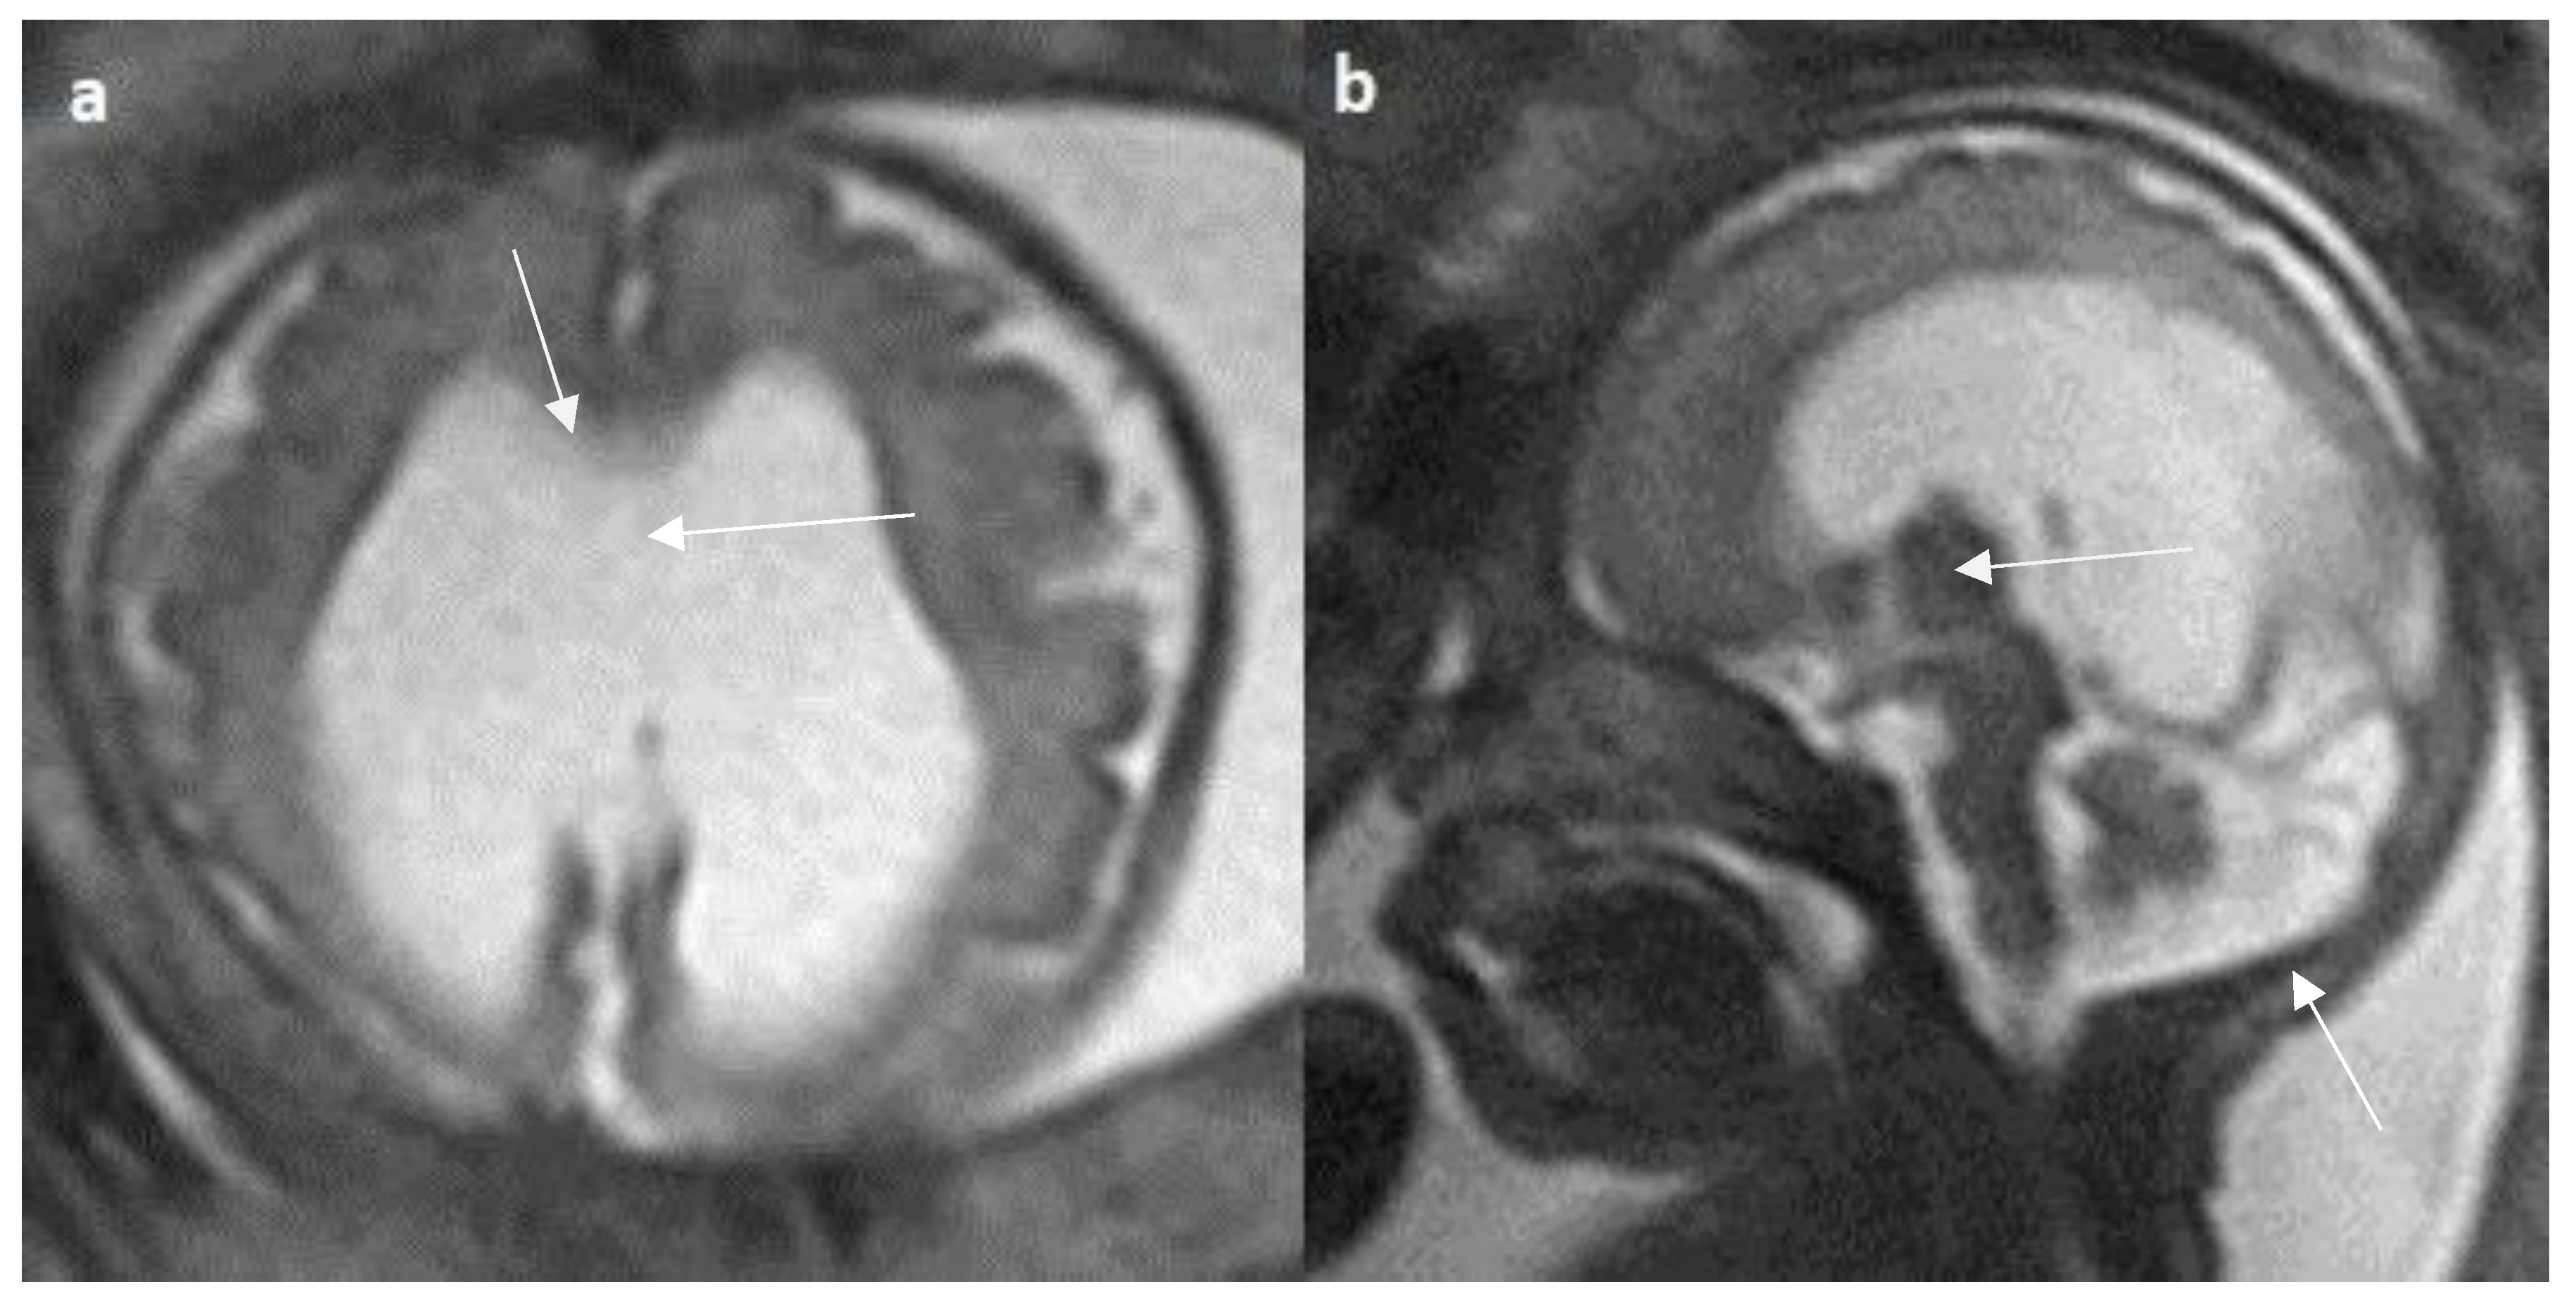

- Manor C, Rangasami R, Suresh I, Suresh S. Magnetic Resonance Imaging Findings in Fetal Corpus Callosal Developmental Abnormalities: A Pictorial Essay. J Pediatr Neurosci. 2020 Oct-Dec;15(4):352-357. [CrossRef]

- Hyun Yoo J, Hunter J. Imaging spectrum of pediatric corpus callosal pathology: a pictorial review. J Neuroimaging. 2013 Apr;23(2):281-95. [CrossRef]